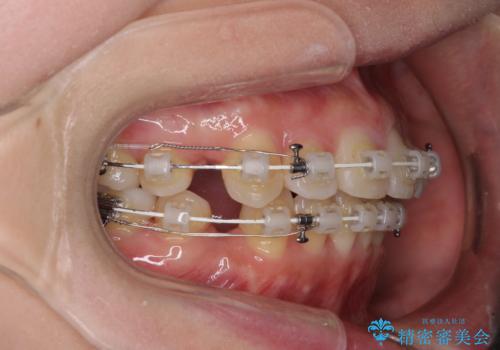

- 矯正装置

- 審美装置

2年~2年半が治療期間の目安でしたが、順調に治療が進み、1年9か月で満足のいく歯列となりました。